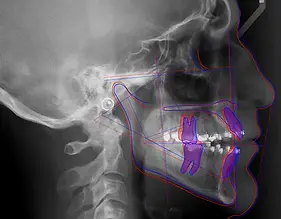

שרטוט ואנליזה

ממוחשבים

בדיקה ממוחשבת על בסיס צילום צפלומטרי, מספקת מידע על זוויות שיניים כדי להקל על תכנון

צילום צפלומטרי

צילום צדדי של הגולגולת, כולל רקמות רכות כמו אף וסנטר, ונעשה לרוב למטרת יישור שיניים אורתודונטי.